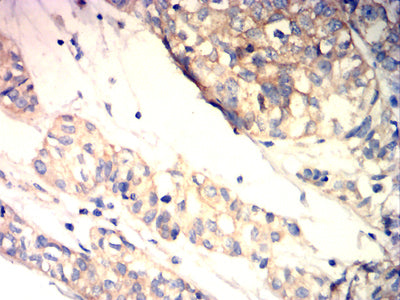

Immunohistochemical analysis of paraffin-embedded human bladder cancer tissues using BRAF mouse mAb with DAB staining.